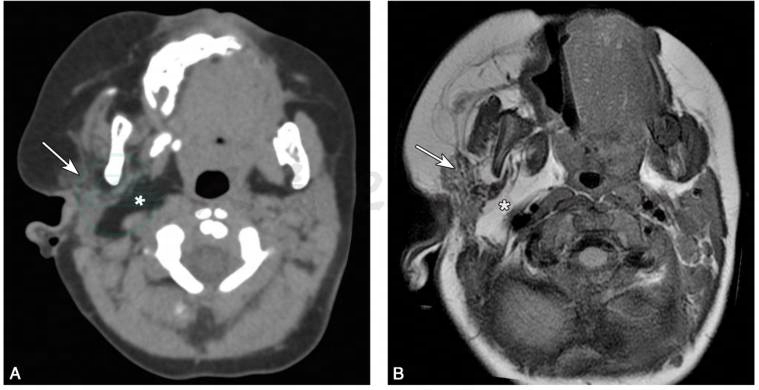

1.X线片可显示病变侧骨质或牙齿增粗(Islam et al,2007)(图1)。 脑 CT和MRI检查显示病侧皮下结缔组织、骨骼及其他脏器均呈肥大改变(Bou-Haidar et al,2010)(图2)。

图2面偏侧肥大症患者脑CT、MRI表现

A.脑CT轴位像;B.脑MRI的T1WI像。可见右侧腮腺和咀嚼肌(箭头)脂肪瘤浸润及相应的大理石纹,以及右侧咽旁间隙扩张(星号)